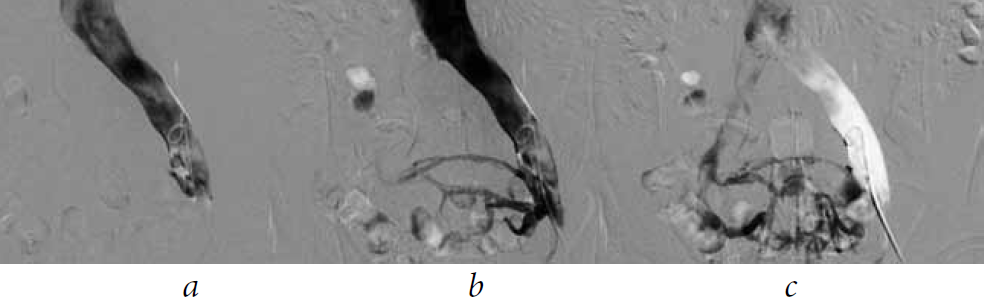

Fig. 3. Antegrade ileocavography of patient M., 39 years old, with pronounced pelvic symptoms (pain, erectile dysfunction, and chronic calculous prostatitis) due to May–Thurner syndrome: (а) antegrade catheterization of the left common iliac vein; (b) note retrograde reflux and contrast of the venous plexus of the small pelvis (collateral circulation) with the introduction of radiopaque substance; (c) after contrasting the venous plexus of the small pelvis, the radiopaque substance is redistributed into the right common iliac vein. The diameter of the right common iliac vein is 1.4 times smaller than the diameter of the left common iliac vein

Fig. 4. Antegrade Ileokavagrafiya patient M., 39 years old, from 28.03.2017. Compression of the left common and left external iliac veins is noted. Operative access from the left popliteal vein. The position of the patient on the stomach